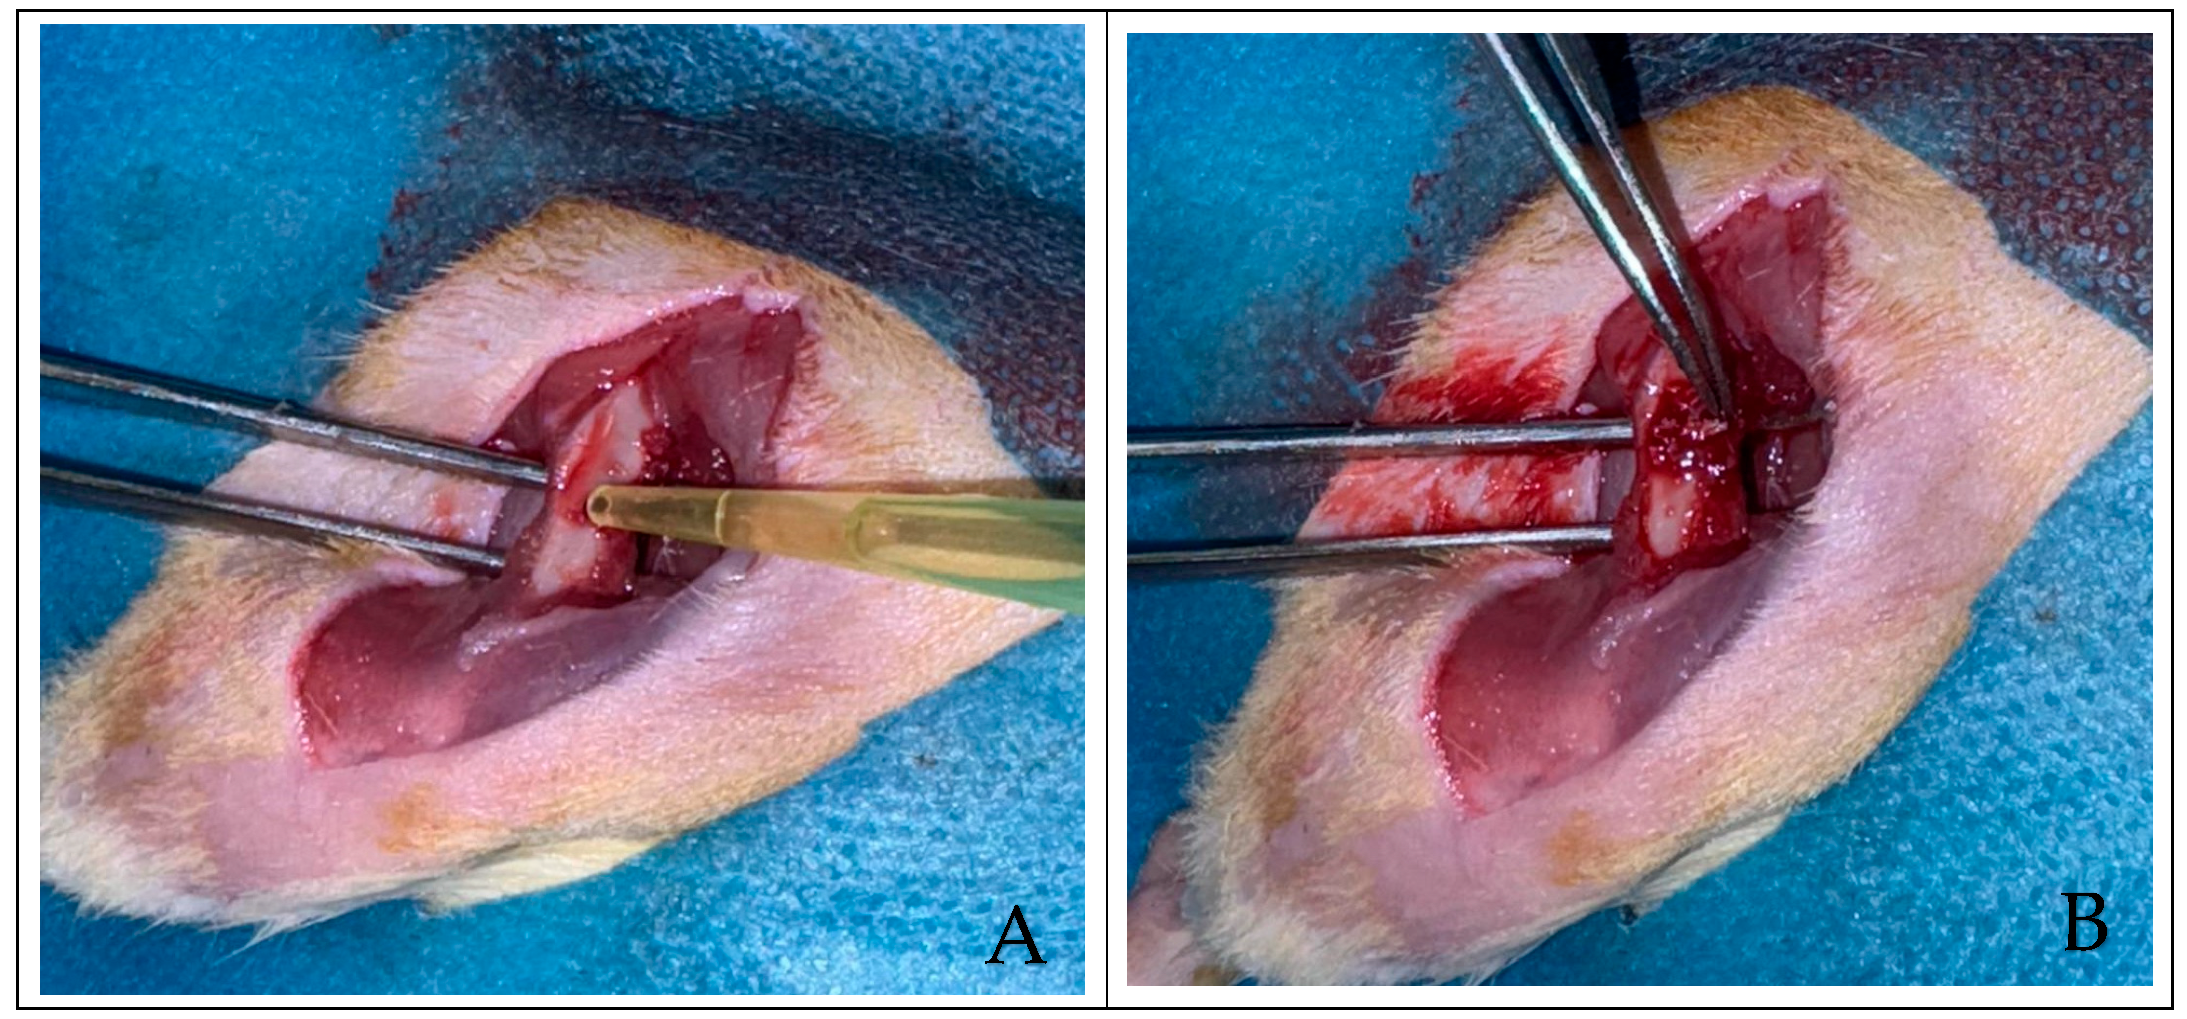

2.3. Experimental Protocol